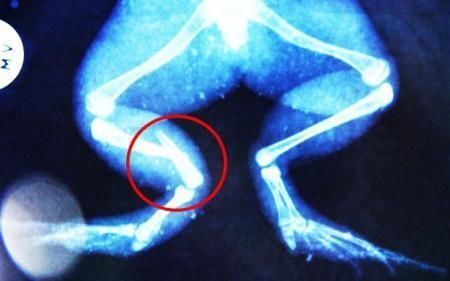

布魯萊的主人,居住在南非約翰內(nèi)斯堡附近的62歲的安妮·米恩斯說:“我對(duì)這只青蛙如此關(guān)心,人們一定認(rèn)為我瘋了,但是我無法眼睜睜看著它那么痛苦。青蛙因其靈活的腿腳而著稱,一想到布魯萊的腿里要留下一個(gè)薄金屬片,我就感到心痛。然而我知道,如果不進(jìn)行手術(shù),布魯萊以后就沒辦法動(dòng)彈了。因此我匆匆趕到獸醫(yī)那里,央求他給這只可憐的青蛙動(dòng)手術(shù)。這位獸醫(yī)整天救助小貓小狗,他很難理解為什么我這么擔(dān)心一只青蛙,但是最終他還是答應(yīng)了給布魯萊做手術(shù)。手術(shù)后是幾個(gè)小時(shí)的焦急等待,我們希望它能快快蘇醒過來。不過現(xiàn)在它的傷口已經(jīng)愈合,又能在花園里跳來跳去了。X光照射顯示,它會(huì)恢復(fù)的跟以前一樣。”

野生生物專家安妮經(jīng)常為學(xué)校寫教材,她認(rèn)為這是人類第一次通過手術(shù)給一只青蛙接斷腿。在手術(shù)開始階段,獸醫(yī)把少量給狗用的麻醉藥注入到這只青蛙體內(nèi),讓它失去知覺。然后他在布魯萊的斷腿上切開一個(gè)小口,把一根小鋼針植入腿里。最后獸醫(yī)給它縫了9針,把切口縫合在一起。僅僅幾周后,布魯萊就能在安妮家附近活動(dòng)了。這只青蛙大約已有25歲,主要以嚙齒動(dòng)物、蛇和其他青蛙為食。布魯萊所屬的牛蛙種群正在不斷減小,目前只能在非洲南部的濕地里才能看到這種青蛙。